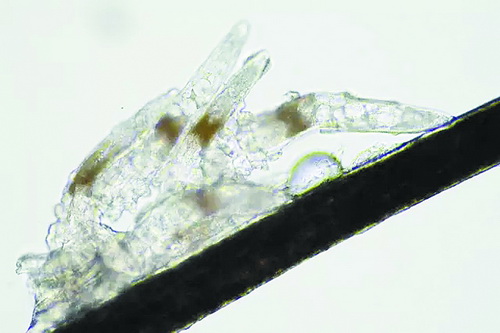

顯微鏡下長在睫毛中的螨蟲

冬天來了,氣溫降低,睫毛上的“隱形殺手”蠕形螨卻沒有要冬眠的意思。廈門大學附屬廈門眼科中心11月初開設(shè)蠕蟲性瞼緣炎門診以來,每天來查螨的市民都特別多,短短一個多月,已有近千人在顯微鏡下見到長期寄居在自己睫毛上,朝夕相處,卻素未謀面的蠕形螨。